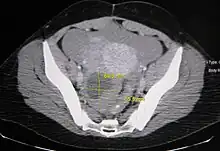

Ovarian cysts are usually diagnosed by pelvic ultrasound, CT scan, or MRI, and correlated with clinical presentation and endocrinologic tests as appropriate.[15] Ultrasound is the most important imaging modality, as abnormalities seen in a CT scan sometimes prove to be normal in ultrasound.[5][8] If a different modality is needed, then MRIs are more reliable than CT scans.[5]